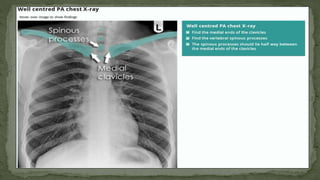

E. Rotation

 Identify the medial ends of the clavicles and select one of

the thoracic vertebra spinous processes that falls between

them.

 The medial ends of the clavicles should be equidistant from

the spinous process, if that’s not the case then the X-Ray is

rotated.